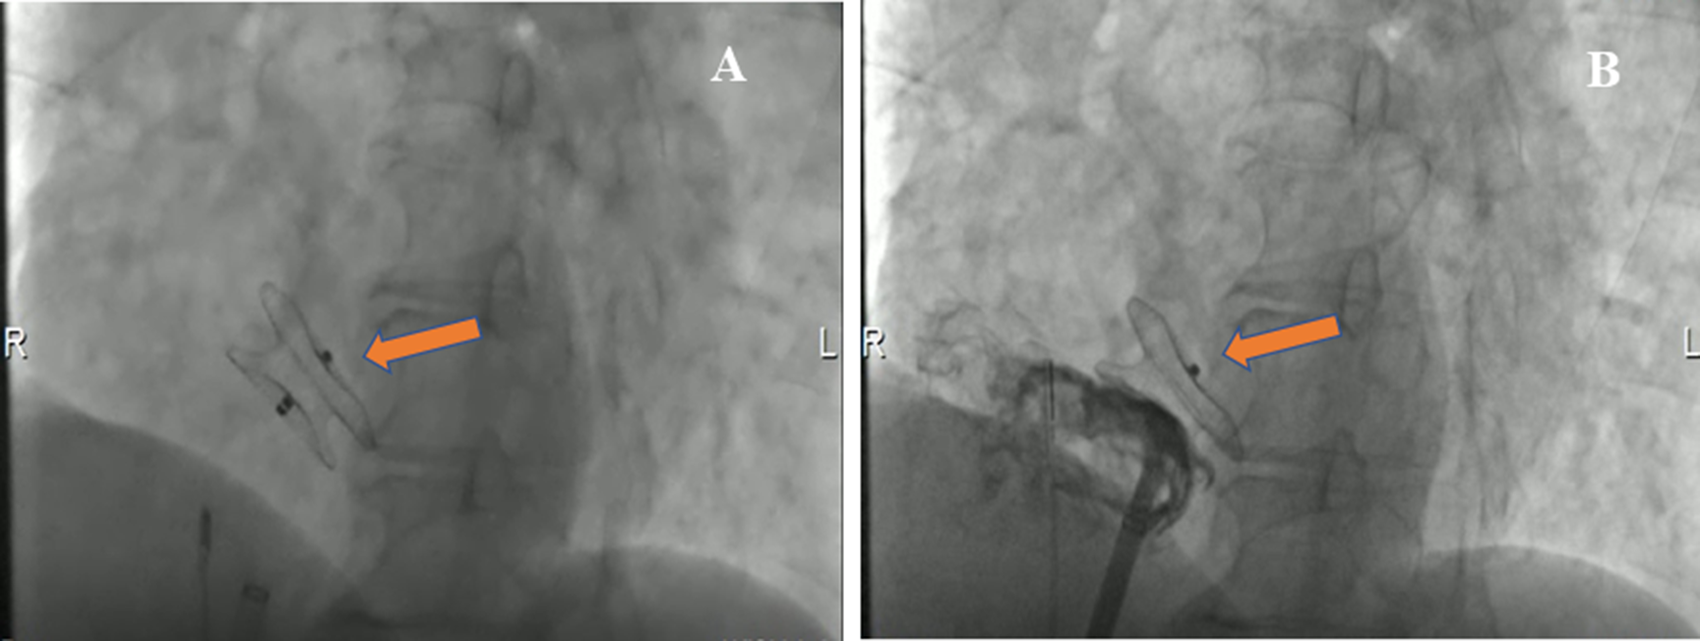

The patient underwent an ASD percutaneous occlusion under the guidance of intracardiac echocardiography (ICE) (Supplementary Movie III). During the operation, the LASH with ASD could be visualized by ICE from different angles. After balloon sizing, an 18 mm septal occluder device (Pushi, Shanghai) was successfully deployed (Figures 3A,B and Supplementary Movie IV). The occluder embraced the thick lipomatous cephalad rim and the thin “normal” caudal rim of the fossa ovalis. The left-to-right shunt disappeared, and no procedural complications, such as erosion or embolization, were observed. The patient was asymptomatic postoperation and followed up in an outpatient clinic (Supplementary Figures 1A–C). The atrial septum no longer increased in thickness. The systolic pulmonary artery pressure was ≈25.8 mmHg after ASD closure.

Figure 3

Cardioangiography (CAG) images demonstrating the closure with a Pushi septal occluder device. (A) CAG image visualized the position of a Pushi septal occluder device during the operation (arrow). (B) CAG image revealed the position of the septal occluder device was good, and there was no shunt between the left atrium and the right atrium after occlusion (arrow).